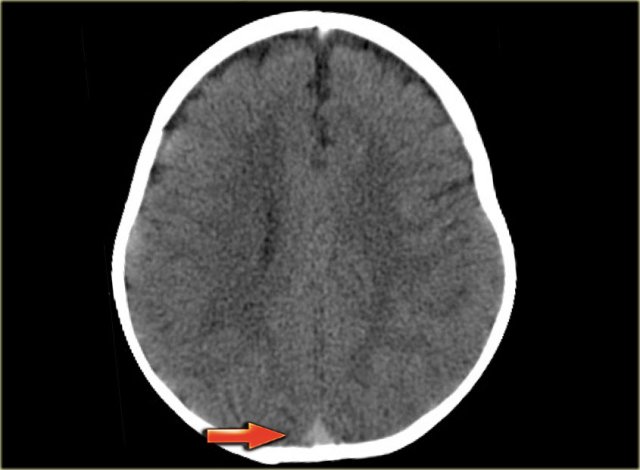

On the left a similar case on MR.

There is a combination of vasogenic edema (red arrow), cytotoxic edema and hemorrhage (blue arrow).

These findings and the location in the temporal lobe, should make you think of venous infarction due to thrombosis of the vein of Labbe.

The next examination should be a contrast enhanced MR or CT to prove the diagnosis.